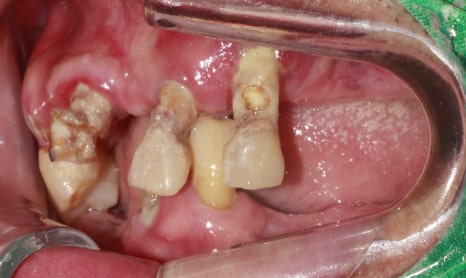

초진사진

촬영:2023년 9월 25일

광주에서 어렵게 발걸음 하신 환자분은

50대 후반의 젊은 나이이시지만

치아만큼은 70대라고 해도 믿어질 정도의

상태로 내원해 주셨습니다.

환자분 인상이 밝은 데에 비해

치아가 군데군데 비어있어

공기가 새기 때문에 발음이 부정확하고

착용하신 마스크 위쪽으로

입 냄새가 강하게 나는 편이었습니다.

그래서 밝은 성격이심에도 불구하고

주변 사람들과 이야기할 때 입을 가리고 말씀하시거나

약간의 거리를 두고 말할 수밖에 없는 게 불편하시다고 말씀하셨습니다.

한 번도 치과 방문을 하지 않았고

치아가 자연스레 부러지고 빠졌던 만큼

환자분의 치아 상태는 생각보다 심각했습니다.

살짝만 건드려도

충치로 인해 치아가 삭아 으스러질 것 같이 치아 조각이 떨어져 나오고 (치아우식)

어떤 치아는 흔들림이 매우 심했습니다(치주염)

건강한 치아들과 비교해 보면

잇몸과 잇몸뼈가 단단하게 잡아주는 치아가 하나도 없는 상태입니다.

그리고 어금니가 없다 보니

수직 고경(위턱과 아래턱 사이의 거리)이 완전히 무너진 상태이고

앞니가 너무 흔들거리고 솟아올라와서 걸리지 않게 씹기 위해서

씹는 동작도 비틀어서 하는 상태였습니다.

앞니만 조금 남아있고

어금니가 없음에도 불구하고

틀니조차 사용하지 않으셨던 환자분이라

식사하는데 많이 불편하셨을 것 같네요.